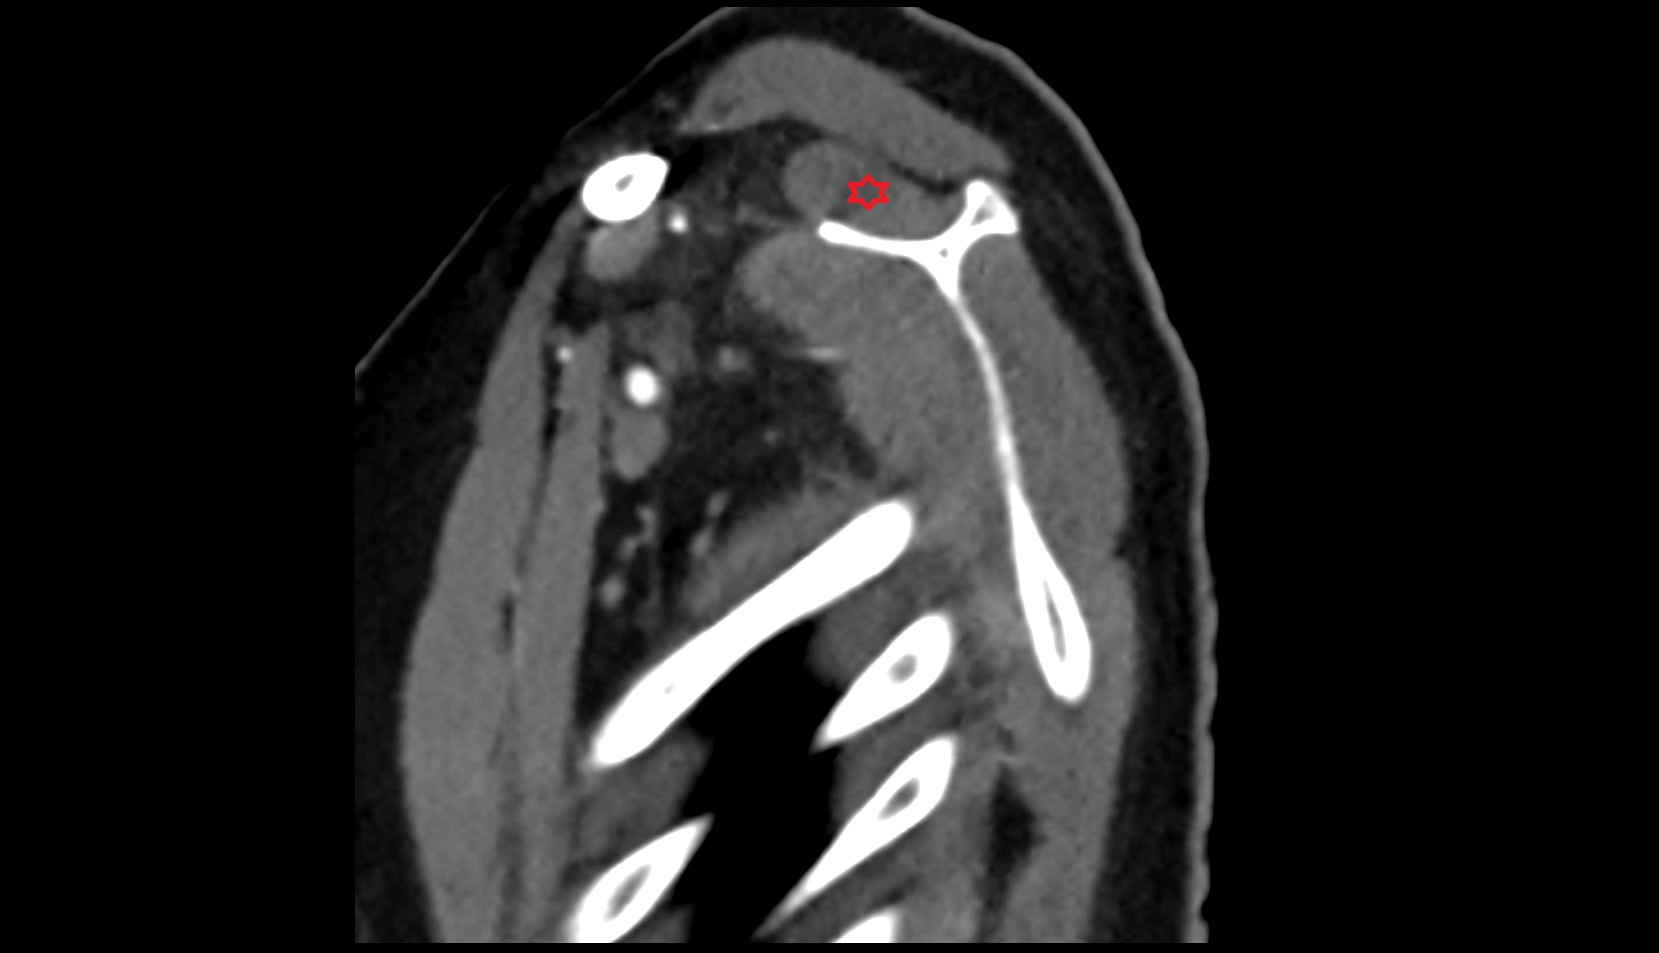

- Shoulder joint (glenohumeral joint)

- Acromioclavicular joint

- Glenoid labrum

- Glenohumeral joint capsule